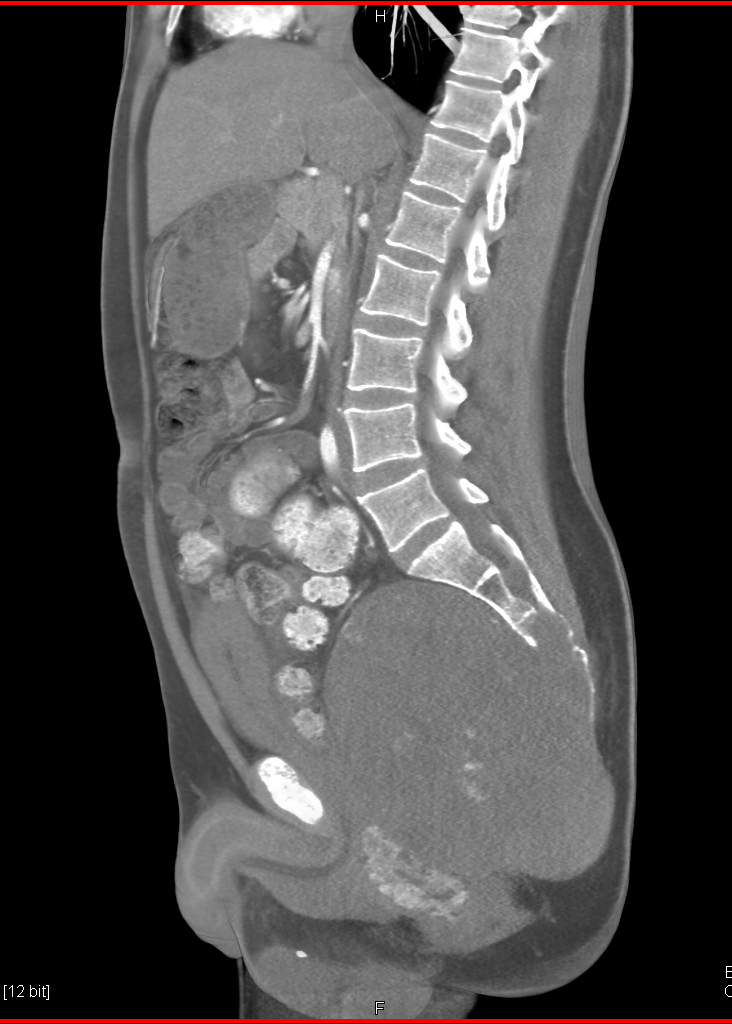

In this patient with rectal pain the most likely dx is?

rectal cancer

chordoma

lymphoma

giant cell tumor sacrum